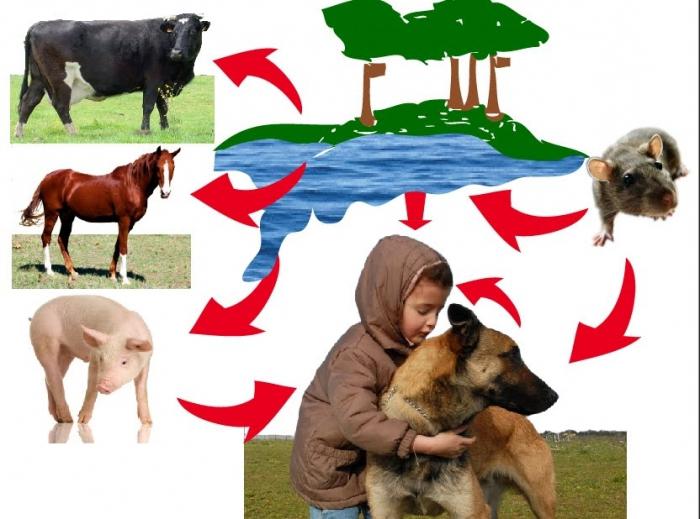

Leptospirosis egy fertőző betegség által okozott Leptospira - mikroorganizmusok élő egész feltételek a magas hő és a túlzott nedvességet. Leptospirosis a leggyakoribb élők a trópusi országokban. Vektor kontroll bevihető :. Kutyák, cickányok, disznók, patkányok, szarvasmarha stb Egy személy megbetegedett leptospirosis, semmilyen veszélyt nem jelent a többi embert.

A fő megelőző módszerek állat-egészségügyi intézkedések, amely azonosításában és kezelésére beteg állatokat. Terjedésének megakadályozása Leptospira Leptospira lehet elérni védőoltás az emberek és állatok. Használata elfogadhatatlanul szennyezett víz forrásokból.